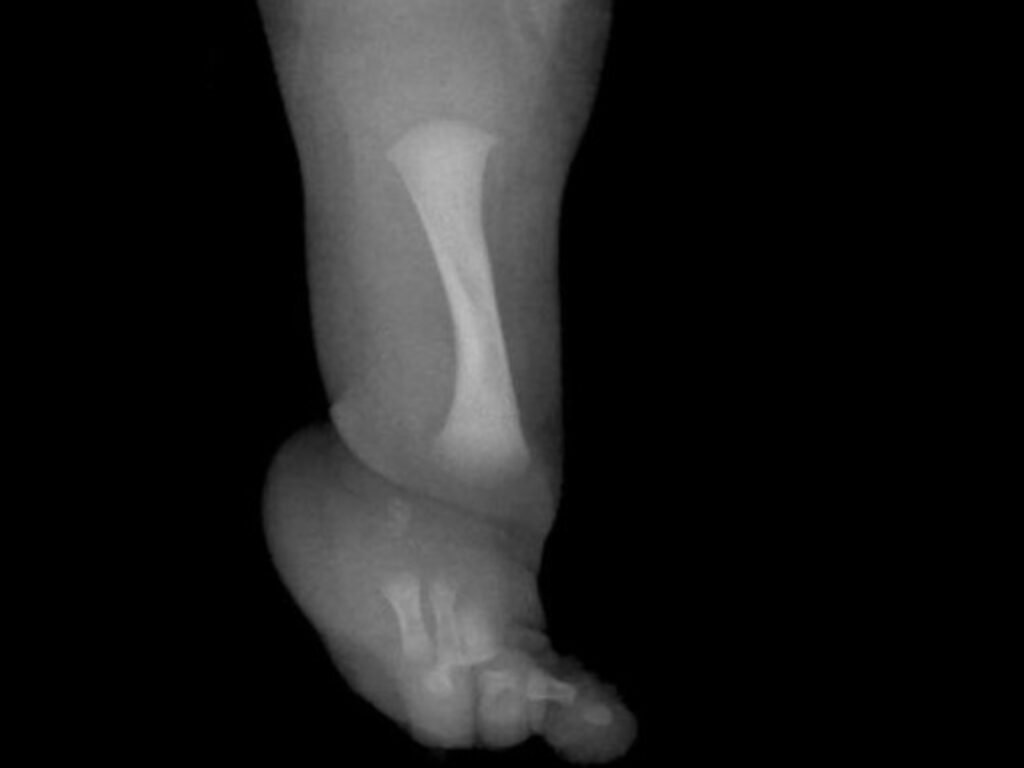

Uncategorized Un nene con una rara enfermedad fue operado para desarrollar un hueso fundamental adminhace 3 mesesMenos de 1 min15,0 Vistas Un niño de nueve años se ha sometido en el Reino Unido a una cirugía pionera. Es para menores que tengan hemimelia fibular. Acciones: TE RECOMENDAMOS Uncategorized Kat DeLuna – Mala Mía hace 3 días Uncategorized Con una gran actuación de Dibu Martínez y un gol agónico de Buendía, el Aston Villa venció al Arsenal y arde la punta de la Premier League hace 5 meses Uncategorized When We Were Young Festival in Las Vegas Announces 2026 Hiatus: ‘This Isn’t Goodbye’ hace 2 meses Uncategorized Racing jugó casi todo el partido con diez y no pudo aguantar a Barracas Central, que se llevó un empate hace 2 semanas Uncategorized Chris Jedi Ft. Anuel AA y ROA – Netflix And Chill hace 4 meses